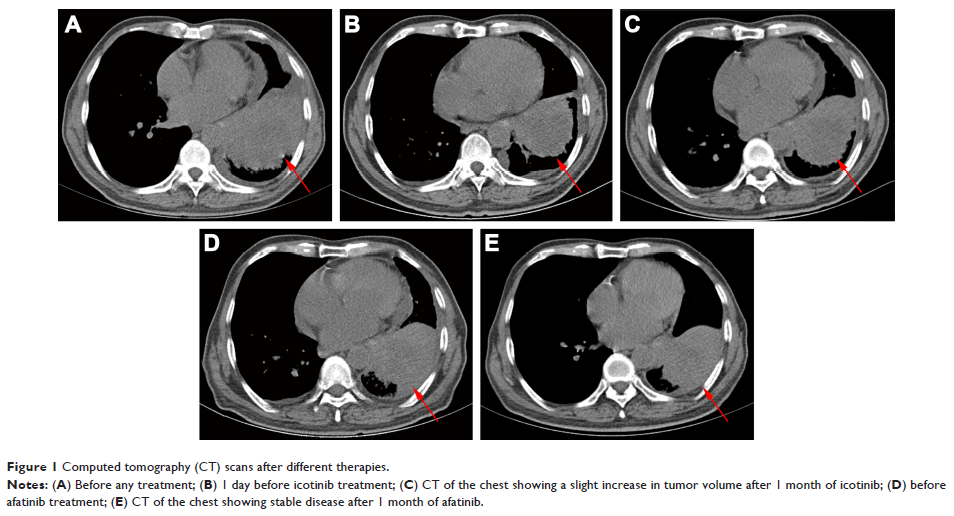

- 作者:Yan Gao, Aihong Zheng, Xiuming Zhu, Jia Song, Qian Xue

- 期刊:OncoTargets and Therapy